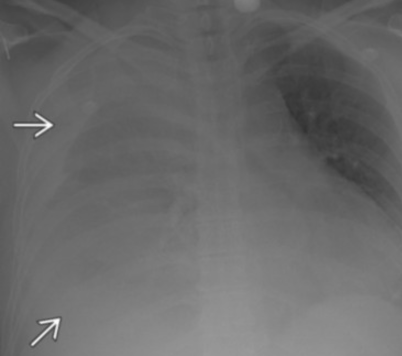

Hemothorax avec saignement actif intercostal embolisé

Hemothorax hémo hemo thorax